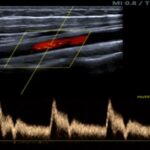

En las Imágenes A y B se valoran las arterias del eje carotídeo, presentando carótida común, externa e interna: flujos anterógrados laminares conservados con velocimetría conservada.